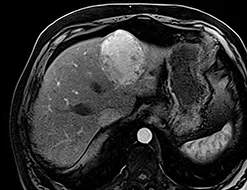

La cicatrice de thermoablation se présente sous forme d’une image nodulaire avasculaire, spontanément hyper intense T1 avant injection, en rapport avec la nécrose de coagulation (figure 2).

Une récidivé loco-régionale se présente sous forme de prise de contraste nodulaire sur les berges de cette cicatrice. Les séquences en pondération T2 ou en diffusion pour diagnostiquer la récidive sont plus difficiles à interpréter car il persiste longtemps après le geste une hyper intensité T2 au sein ou au pourtour de la cicatrice.

| Carcinome hépato-cellulaire de 45 mm de diamètre, typique en IRM chez un patient de 75 ans, porteur d’une cirrhose éthylique et dysmétabolique incomplètement sevrée, Child A avec une alfafoetoprotéine normale. La clairance au vert d’indocyanine très pathologique à 34% à 15 min (Nle <15) a fait contre-indiquer un traitement chirurgical. | |